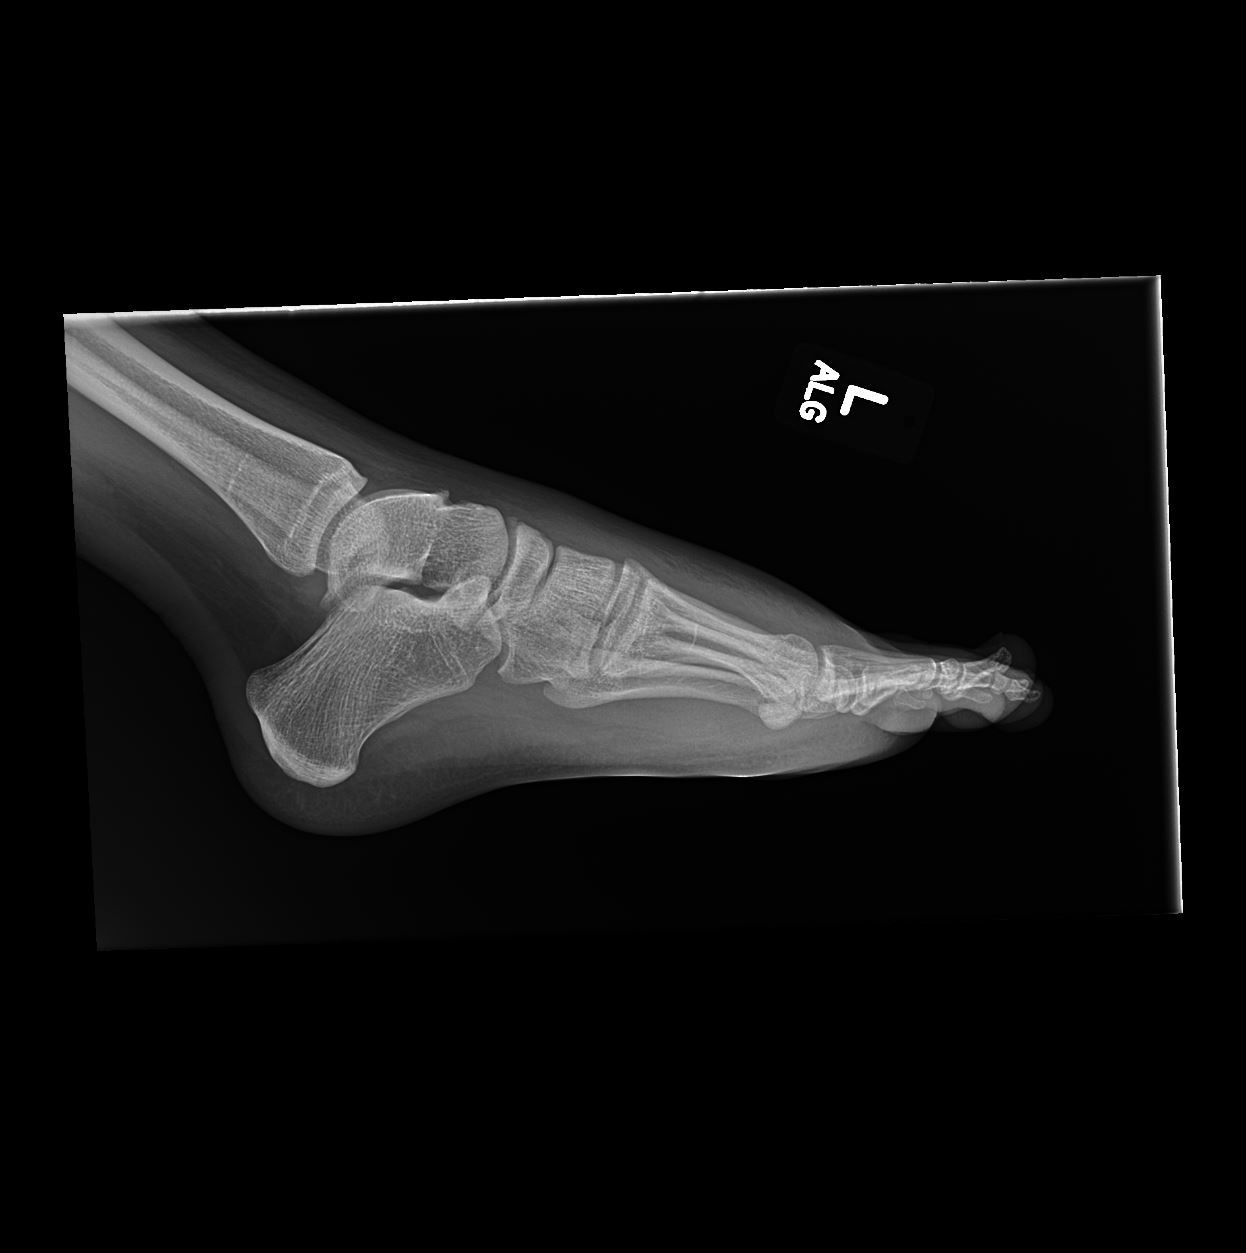

Young male presents with foot pain after injury. What most likely represents the imaging finding?

Case: Young male presents with foot pain after injury. What best represents the imaging findings?